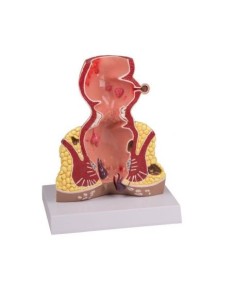

3B Modèle scientifique et anatomique : Pathologies de l'intestin K55